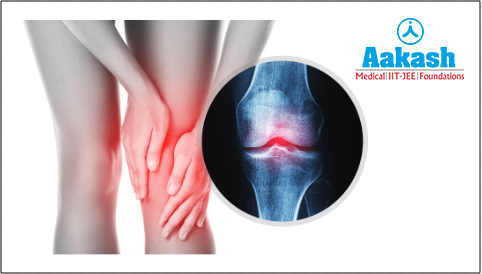

The condition of osteoarthritis commonly develops in the knee joint. This is because the knees bear the body weight, extreme stress, twists, and turns of the whole body. It often affects both knees.

Fig: Osteoarthritis in the knee joint